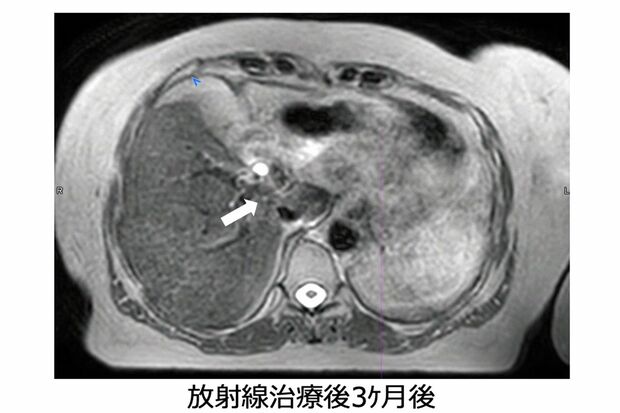

放射線治療後3か月では、ほとんどがんが見えなくなっている(画像提供:GenesisCare)

[写真 4/6枚目] 放射線治療後3か月では、ほとんどがんが見えなくなっている(画像提供:GenesisCare)